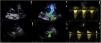

The case concerns a four year old female refugee who was referred to our hospital's Pediatric Cardiology Department by the camp's general doctor, after discovering a systolic murmur on physical examination. The patient's noteworthy medical history consisted of a percutaneous cardiovascular operation while an infant, for which there was no documentation available. On inspection, the patient was alert, non-dyspneic, non-cyanotic with an expected growth and weight for his age. His arterial pressure was 110/75mmHg without radio-radial or radio-femoral pulse delay. On auscultation, there was a 3/6 systolic crescendo/decrescendo murmur in the left precordial area, without a palpable thrill. An echocardiogram was performed, where an echodense structure was noted in the region of the ductus arteriosus (Video 1 and 2), causing moderate stenosis in both left pulmonary artery (Figure 1, panel a–c; Video 3) and descending aorta (Figure 1, panel a–f; Video 4–6) through protrusion.

(a) Modified parasternal short axis view of the main pulmonarty artery (PA) and its bifurcation. (b) Same view with colour doppler, revealing turbulent flow in the left pulmonary artery (LPA). (c) Doppler derived mean pressure gradient across the LPA stenosis was estimated at 20 mmHg. (d) Suprasternal view of the aortic arch where the echodense structure is visualized. (e) Same view with colour doppler aliasing. (f) Doppler derived mean pressure gradient across the descending aorta stenosis was 19 mmHg.